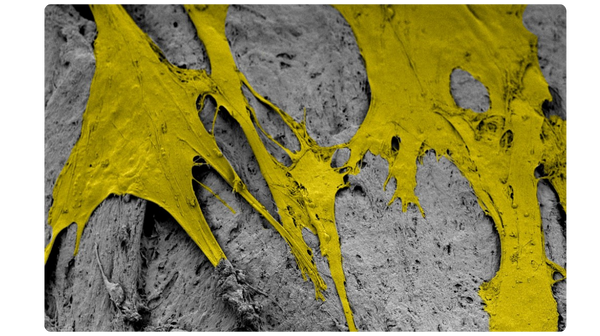

The unique surface characteristics of PliaFX fibers set the standard for osseointegration.4-6 With a large surface area and well-structured demineralized cortical fibers, PliaFX provides a solid scaffold that fosters cellular viability and proliferation.4† Our proprietary processing method creates favorable porosity and microhook protrusions, improving the graft's osteoconductivity.4,10†

Scanning electron microscopy (SEM) at 3000x magnification. Images were pseudo colored in Adobe Photoshop to distinguish the cells (in yellow) from the fibers.